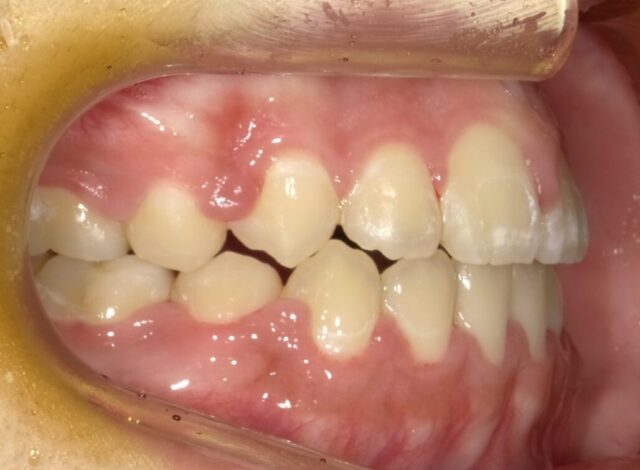

≪右側面観≫

2023年5月

2023年6月

2023年7月

2023年8月

2023年9月

2023年10月

2023年11月

2023年12月

2024年1月

2024年2月

2024年3月

2024年4月

2024年5月

2024年6月

2024年7月

2024年8月

2024年9月

2024年10月

2024年12月

2025年1月